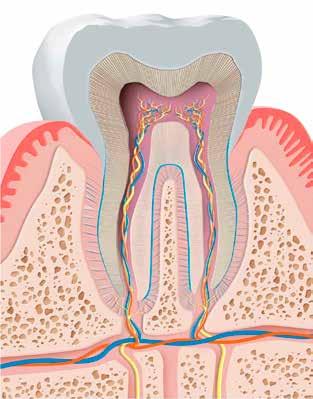

Ahhoz, hogy esztétikai munkánk jelentőségét, az okklúzió kialakításának felelősségét fel tudjuk mérni, mindenképpen a fogak és a fogakat körülvevő csontozat felépítéséig kell visszamennünk. Mindenekelőtt azt kell látnunk, hogy minden szervünk, minden egyes testrészünk valójában egy élő test részegységeként fogható fel, amelyben különböző sejtek dinamikus tevékenysége figyelhető meg, a sejtek életciklusuktól függően állandóan változó közeget adva, életteret biztosítva, milliónyi funkciót ellátva, valójában egy önálló struktúrát alkotnak. Nincs ez másképpen a fogak és a maxilla, valamint a mandibula egységének szemlélésekor sem. A csontozatot felnagyítva folyamatosan változó közeget figyelhetünk meg az oszteoklasztok, oszteoblasztok, oszteociták meg nem szűnő működése kapcsán is. Kollagéntermelés, ásványi anyagszállítás, csontlebontás egyidejű jelenléte tapasztalható. Ha ezeket a folyamatokat, a sejtek működését, nyüzsgő világukat kisfilmként néznénk, bizonyosan elgondolkoznánk azon, hogy ebbe az élő, folyamatosan változó struktúrába, nyüzsgő világba hogyan és milyen módon szólhatunk bele a fogak érintkezésének megváltoztatásakor, illetve hogyan tudjuk ezt a kialakult harmonikus egységet és funkciót megőrizni. Ebbe a dinamikusan változó közegbe kapcsolódnak bele fogaink egy speciális ízületi rendszerrel, az ún. gomphosissal (3. kép). Minden egyes fogat, fogfelszínt is érintő változás erre az ízületi egységre hat. Az „ízületre” ható erők kompenzálását a gyökérfelszínen tapadó, periapikális térben található szalagok (periapikális ligamentumok) végzik, azaz nem csak a fogat rögzítik ebben a térben. Valójában, amikor a fogak érintkezését, a statikus és a dinamikus

okklúziót alakítjuk ki, illetve a helyes artikulációt biztosítjuk, akkor nem teszünk mást, mint egy többízületes egység kialakítását végezzük egy folyamatosan változó közegben (4. kép). Vagyis 2x átlagban 24 (gyökerek számától függ) gomphosis ízület helyes működését próbáljuk biztosítani statikus és változó közegben a kialakításra váró komplex beavatkozásokkal a fogak érintkezéseinek kialakítása során. Ha ebbe belegondolunk, akkor talán teljesen másképp látjuk a fogak érintkezését, az okklúzió kérdését és problematikáját is. Az élő szövet válaszreakciókat ad. Ahogy a periapikális terület nyomást érzékel, változások indukálódnak a csontban is. A tengelyirányú erők a fogak túlterhelődéséhez vezetnek, a fogak a parodontális résbe nyomódva az ott futó idegeket, ereket összenyomva, a gyökérhártyát terhelve, akár a fogak elhalásához is vezethetnek. A fogakat oldalirányból

3. kép: Gomphosis.

4. kép: A fogak érintkezése egy többizületes okklúziós egységként is felfogható.